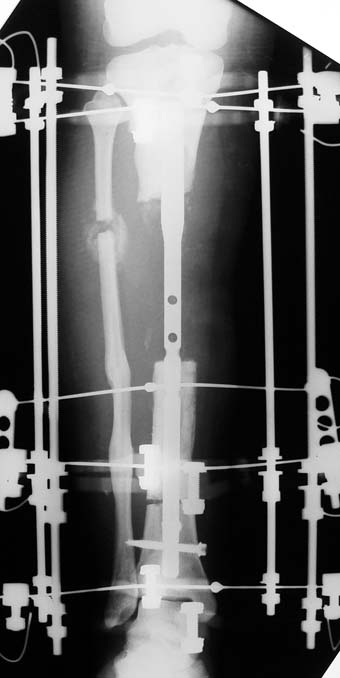

Uygun radikal debridman tüm nekrotik kemik ve yumuşak dokuların çıkartılmasını gerektirir, ve sıklıkla uzuvda instabiliteye neden olur. Kalan kemik ve yumuşak doku defektinin bir şekilde fiksasyonu ve rekonstrüksiyonu gereklidir. İlizarov’un ortaya koyduğu distraksiyon osteogenezi yöntemi, kaynamanın elde edilmesi, deformitenin düzeltilmesi, bacak boy eşitsizliğinin giderilmesi ve segmental defektlerin rekonstrükte edilmesi için başarıyla kullanılmaktadır.

Eksternal fiksatör ile geçen süre (eksternal fiksasyon indeksi), gereken distraksiyon miktarına bağlıdır ve bu süre boyunca bazı komplikasyonlarla karşılaşılabilir. Distraksiyon dönemi sona erdikten sonra, distraksiyon süresinin iki katını aşan konsolidasyon döneminde hastalar eksternal fiksatörü zorlukla tolere edebilirler. Yeterli konsolidasyon sağlanmadan eksternal fiksatör çıkartılırsa ise kırıklar, deformite ve kısalık oluşabilir. Hastanın fiksatör ile birlikte geçirdiği sürenin azaltılması ve böylece hasta konforunun ve aktivite düzeyinin arttırılması için intramedüller çivi üzerinden uzatma yöntemi uygulanmaktadır. Bu yöntemde distraksiyon dönemi sona erdiğinde kemiğin içindeki çivi statik olarak kilitlenmekte ve eksternal fiksatör çıkartılmaktadır. Stabilizasyon intramedüller çivi tarafından sağlandıktan sonra konsolidasyon dönemi gerçekleşmektedir. Bu şekilde hem eksternal fiksatörün uzun süre kalmasından hem de erken çıkartılmasından kaynaklanan komplikasyonların önüne geçilmektedir.